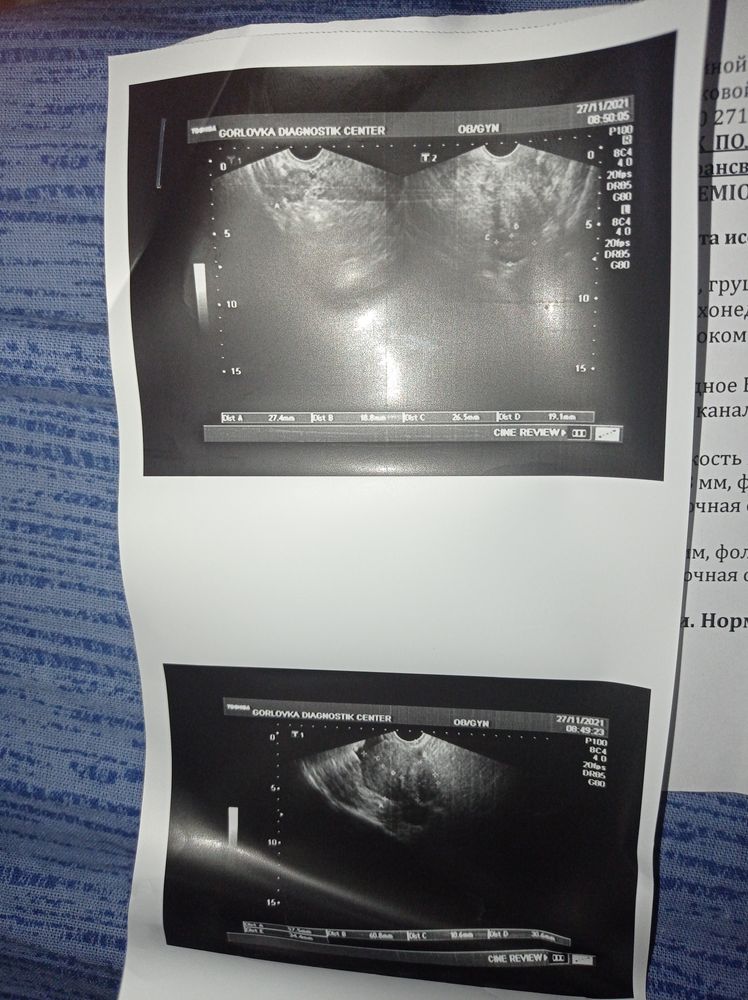

Добрый день, подскажите пожалуйста, месячные начались раньше срока, на 3й день начал очень сильно тянуть живот поехала в приёмное отделение сказали все нормально, а боль такая что хожу с трудом и почему то сделала тест и он положительный... На УЗИ тоже ничего не увидели. Что это может быть???